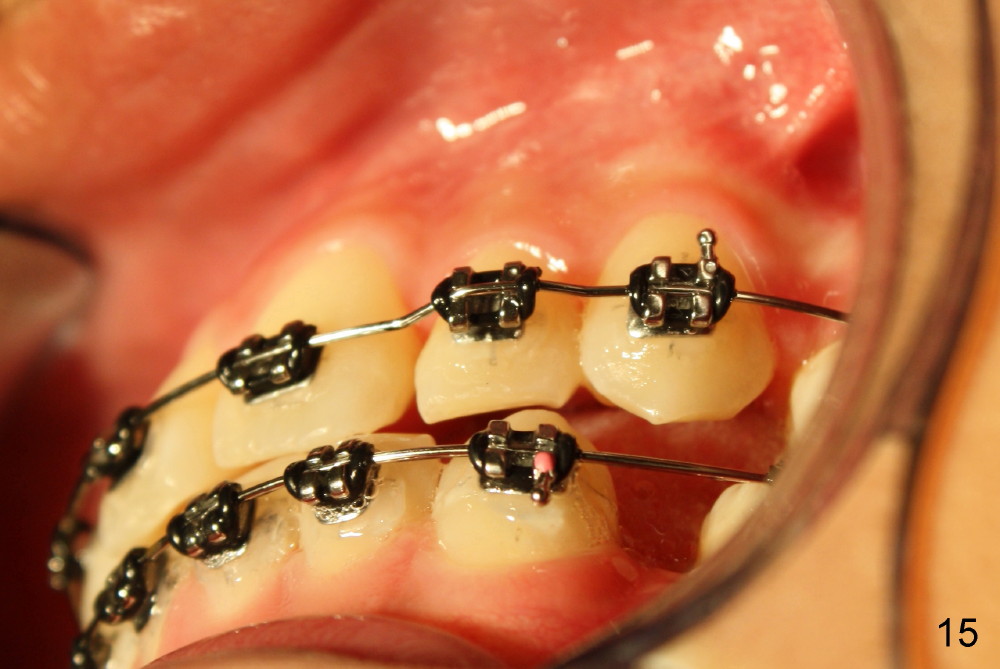

A 13-year-old boy has severe crowding (Fig.1-5). Four of the first bicuspids were extracted on 02/17/2014. Full mouth brackets or bands (except #18) were placed on 03/27/2014. Alignment improved 2 months later (Fig.11, 05/24/2014). The upper 18 ss wire was modified (Fig.12), and fixed with alastiks (Fig.13,14). One month later (07/01/2014), local alignment also improved (Fig.15); the upper modification is confined to one tooth.